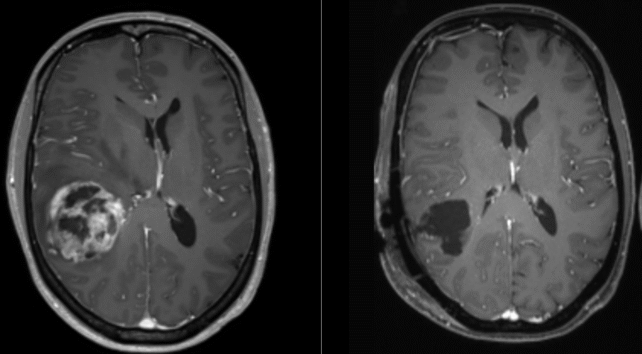

Zdroj foto: Ars Neurochirurgica/Wikimedia/CC 4.0